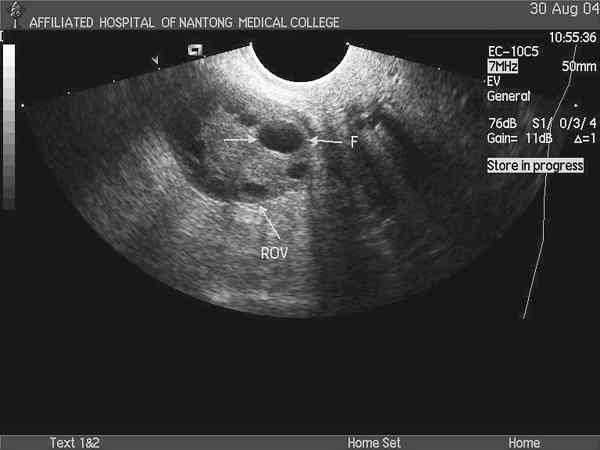

试管自然周期方案促排取卵对卵泡大小的要求分析

冰糖娃娃

试管自然周期方案促排卵泡长到18mm以上就可以开始取卵了。不过由于每个患者的身体情况不同,所以对于卵...